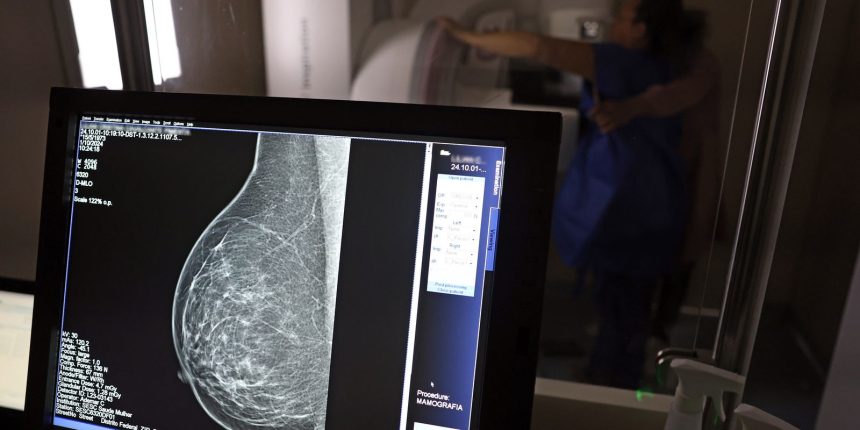

No Outubro Rosa, o Instituto Nacional de Câncer (Inca) estimou 73.610 novos casos este ano no país. É o câncer que mais mata mulheres no Brasil. As mulheres em tratamento pela doença têm o direito de receber o auxílio-doença ou o benefício de prestação continuada.

A vice-presidente da Comissão de Previdência Social Pública da Ordem dos Advogados do Brasil do Rio de Janeiro (OAB-RJ), Danielle Guimarães, destaca que o câncer de mama é uma das doenças que mais afetam mulheres no Brasil, impactando não apenas a saúde física e emocional, mas também a capacidade de trabalho e a segurança financeira das pacientes.

- Falta de acesso a mamógrafos limita prevenção do câncer de mama.